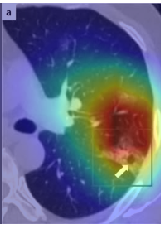

A wide variety of typical and atypical CT abnormalities have been reported for COVID-19 patients in various studies [58, 59]. So, we tested our models on external CT images extracted from these two publications as they feature typical findings of COVID-19 pneumonia marked by specialists. In order to make sure that not any of the extracted images are unintentionally included in our datasets, specifically the COVID19-CT dataset, we use the model trained on the SARS-CoV-2 dataset. First, the InceptionV3 model is employed to classify the extracted CT images. The model is able to correctly classify the given CT images as COVID-19. Second, in order to interpret the model’s generalization capabilities, we apply the Grad-CAM technique to visualize the regions of abnormalities that are considered. By assessing the different CT images in Figure 15, we can see that the model accurately localizes the disease-related regions. Even more interesting is the fact that the model ignores any specific marks in the images like letters and only localizes the COVID-19 related regions. These visual explanations show the success of our models to learn relevant, generic visual features related to COVID-19 and are capable to correctly classify CT images outside the datasets on which they are trained.

Figure 16 shows various CT scans where only one lung is visible. The CT scans are also extracted from the paper [58] and show different CT manifestations of COVID-19 pneumonia marked by red squares. The InceptionV3 model is capable to classify them correctly as COVID-19, although it is trained on CT scans where the entire lung is visible. Intriguingly, when applying Grad-CAM we can see that all regions of abnormalities are accurately localized. This also proves the potential of our model to detect COVID-19 abnormalities in CT images outside the dataset used for training.